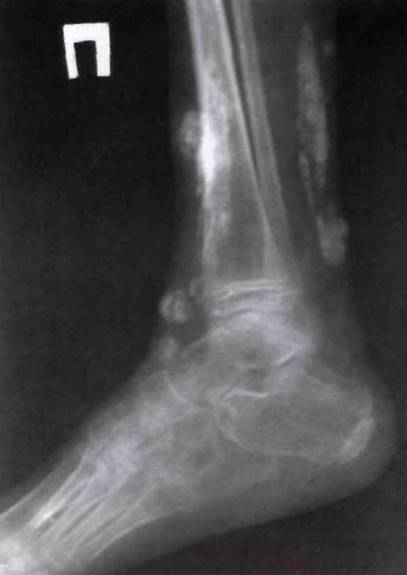

Рис. 23-4. Поражение суставов предплюсны (тарзит) и теносиновиты области наружной и внутренней лодыжек у больного ЮАС.

Рис. 23-5. Рентгенограмма стоп больного ювенильным спондилоартритом: деструкция в суставах предплюсны, крупные остеофиты, эрозии, резкое сужение щелей.

Рис. 23-10. Выраженный ахиллобурсит справа, теносиновиты области внутренней лодыжки больного ЮАС.